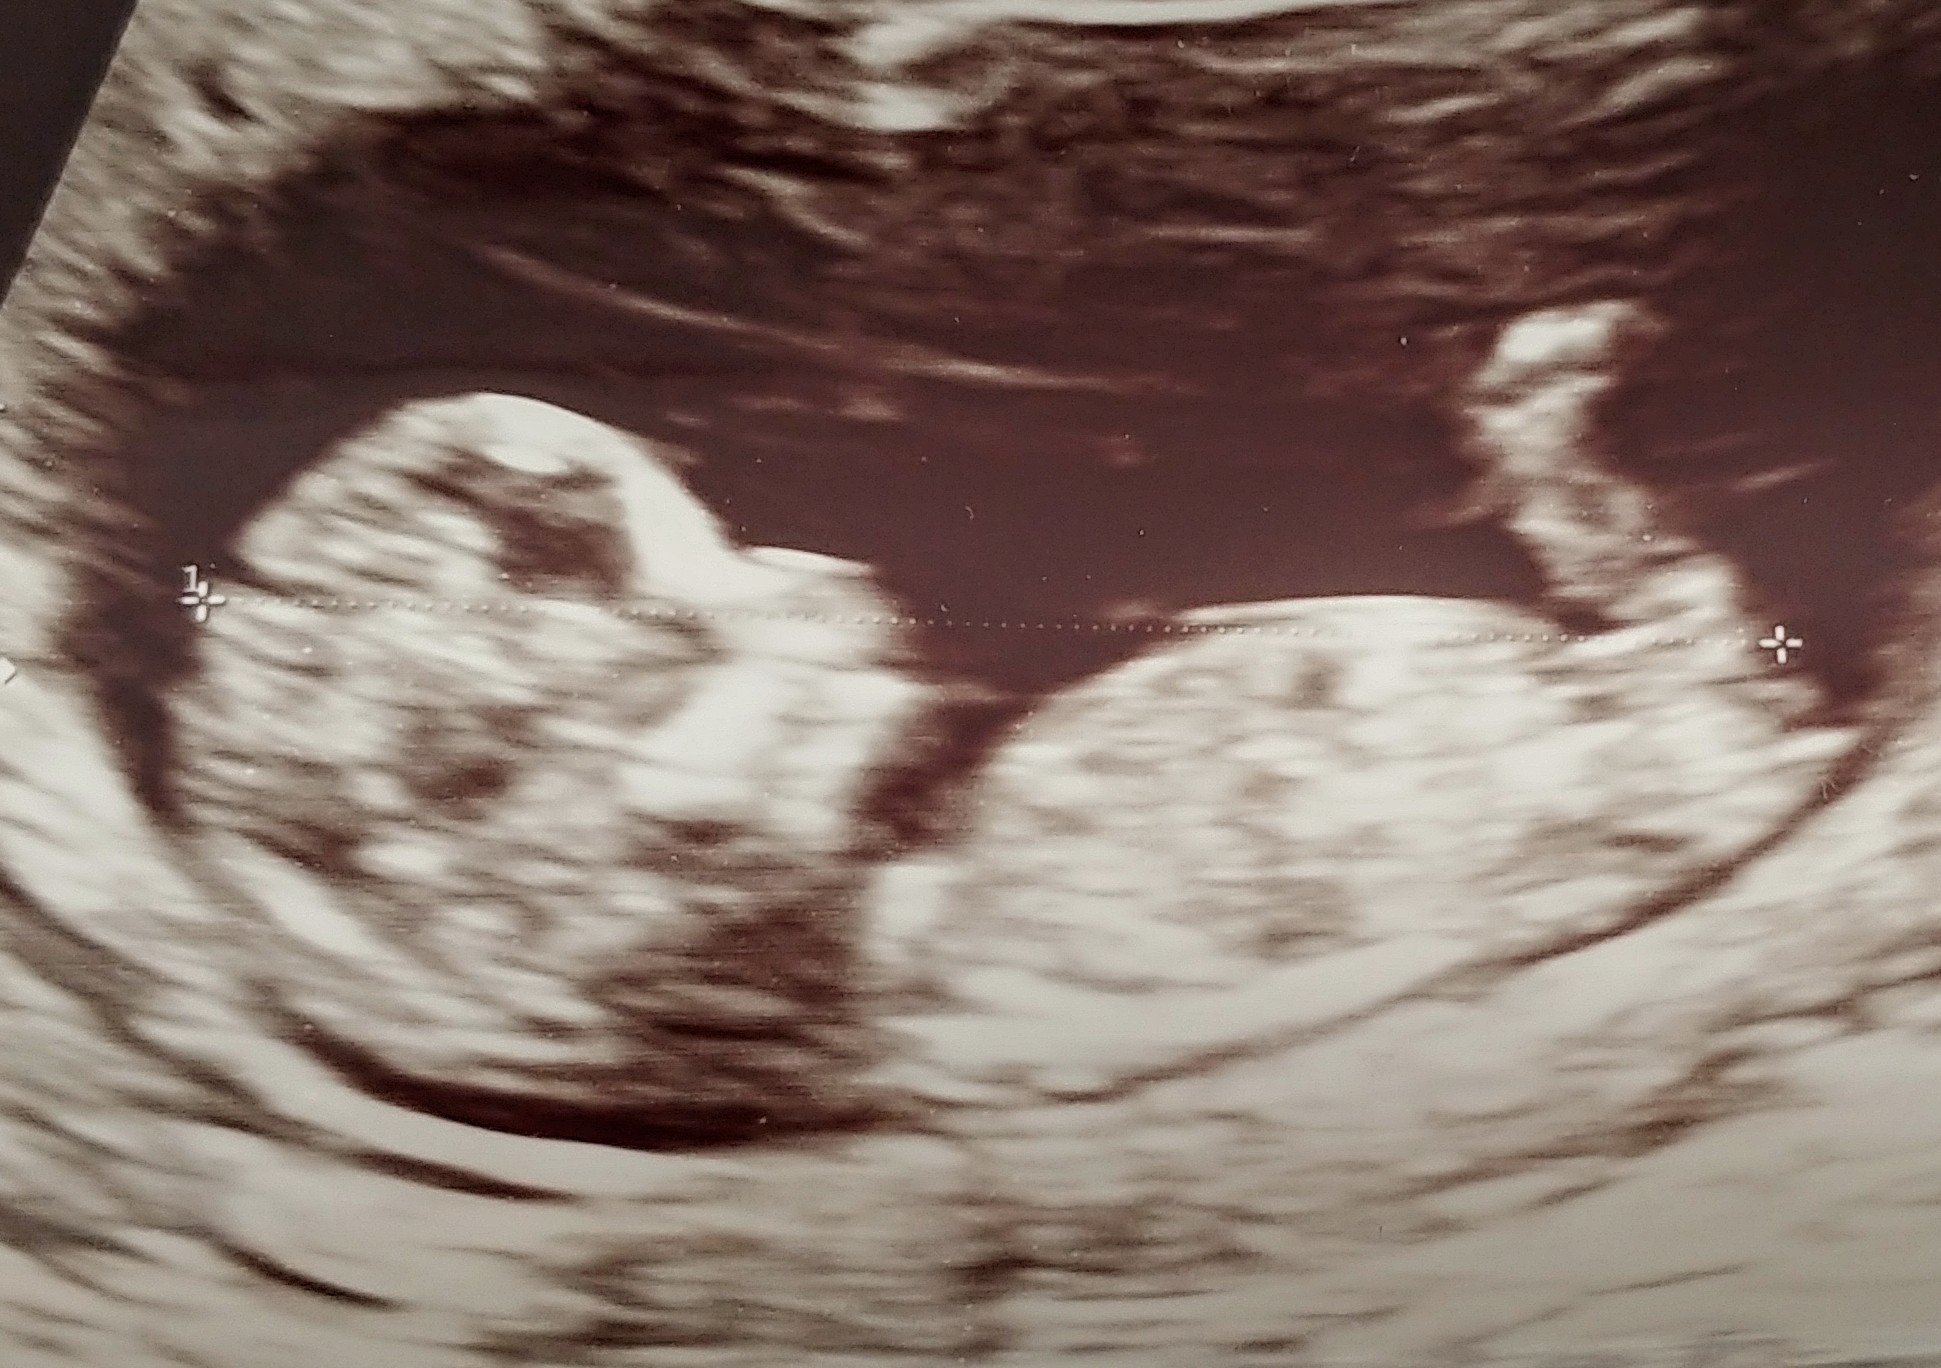

a to moja mała małpka🍼👶

Załączniki

• 20200610_185608_HDR~2.jpg

20200610_185608_HDR~2.jpg

464,8 KB · Wyświetleń: 82